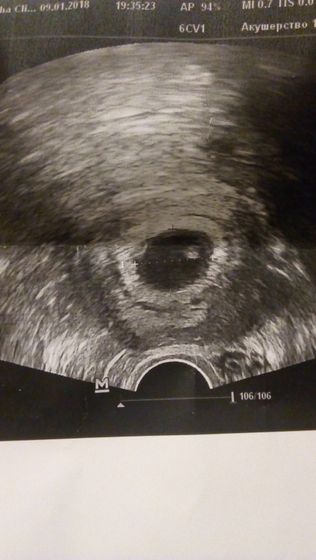

Нам 5 недель и 3 дня, чувствую себя ну просто ужасно, с доченькой все было не так!!! Мало того, что теперь Любой автобус мой самый злейший враг, так и еще после каждого приема пищи, дует так, как будто ела неделю.Хочу мясного, наверно я не когда его так не ела как сейчас.И самое ужасное, меня бесит почти все, ну точнее я спокойно, но стала заводиться с пол оборота… зато ,слышала стук сердечека своего маленького займу ух, что же будет дальше)Зато большое счастье, буду мама в квадрате))))